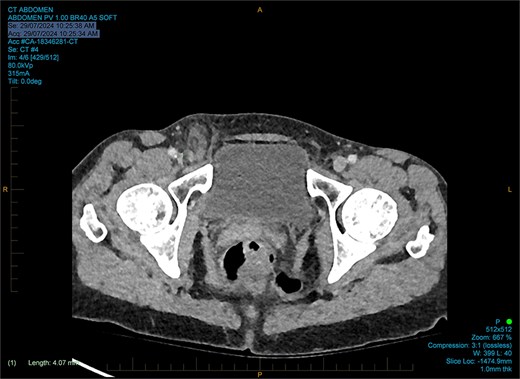

She had normal inflammatory markers and lactate. A computed tomography (CT) scan was reported as a direct right inguinal hernia containing the appendiceal tip (an Amyand’s hernia). There was adjacent soft tissue density and fat stranding raising the possibility of incarceration (Figs 1 and 2).